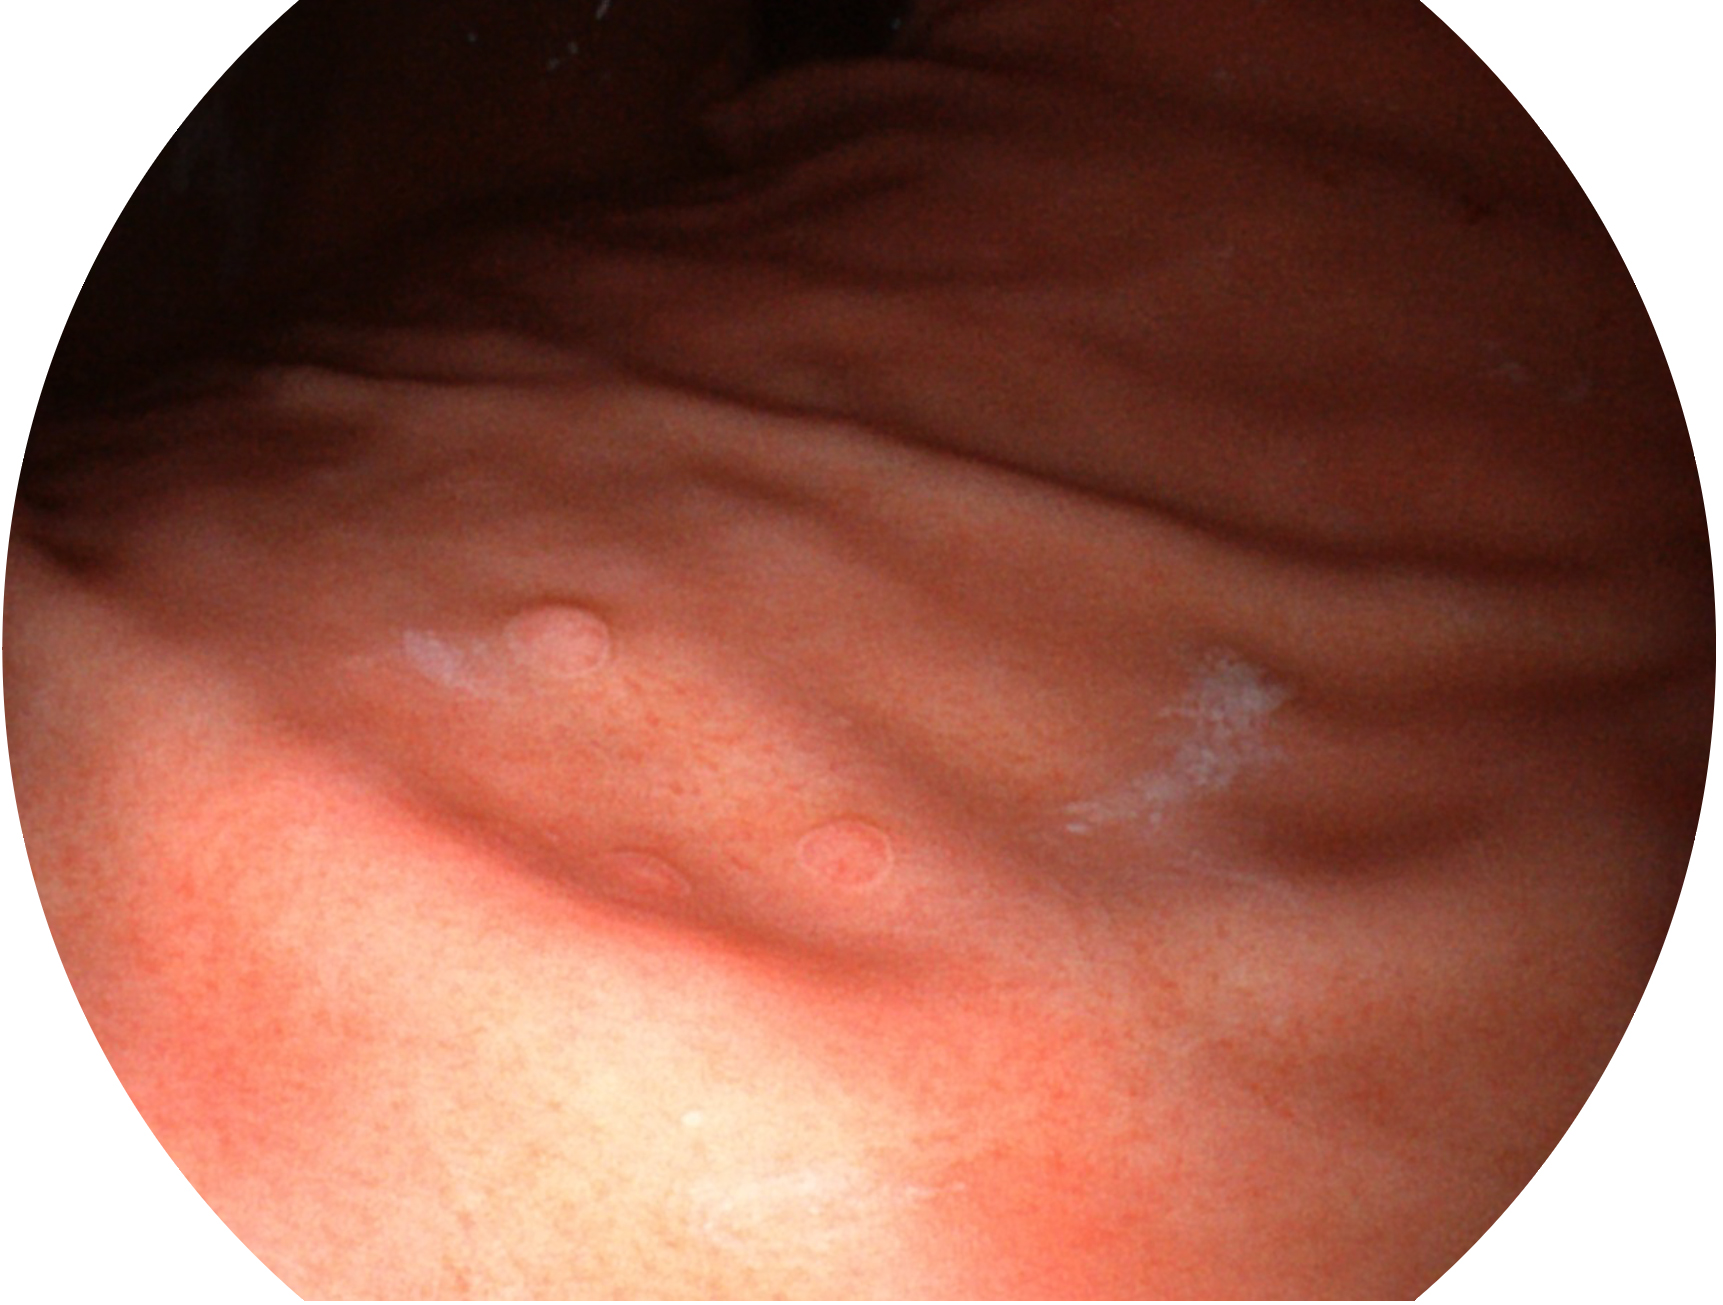

開立新開發(fā)的內(nèi)鏡染色技術(shù),主要是基于多波長(zhǎng)LED 光源的開發(fā),VLS-55Q 四波長(zhǎng)LED 光源是由四個(gè)不同顏色的LED光按照相應(yīng)照明模式所規(guī)定的特定發(fā)光比例進(jìn)行合束后形成,合束后形成的照明光的光譜由紅光、綠光、藍(lán)光及藍(lán)紫光這四個(gè)不同的波段范圍構(gòu)成。具有更高光譜自由度,通過光譜比例的控制,實(shí)現(xiàn)了聚譜成像技術(shù),英文全稱為“Spectral Focused Imaging, SFI”,縮寫為“SFI”和光電復(fù)合染色成像技術(shù),英文全稱為“Versatile Intelligent Staining Technology, VIST”,縮寫為“VIST”。